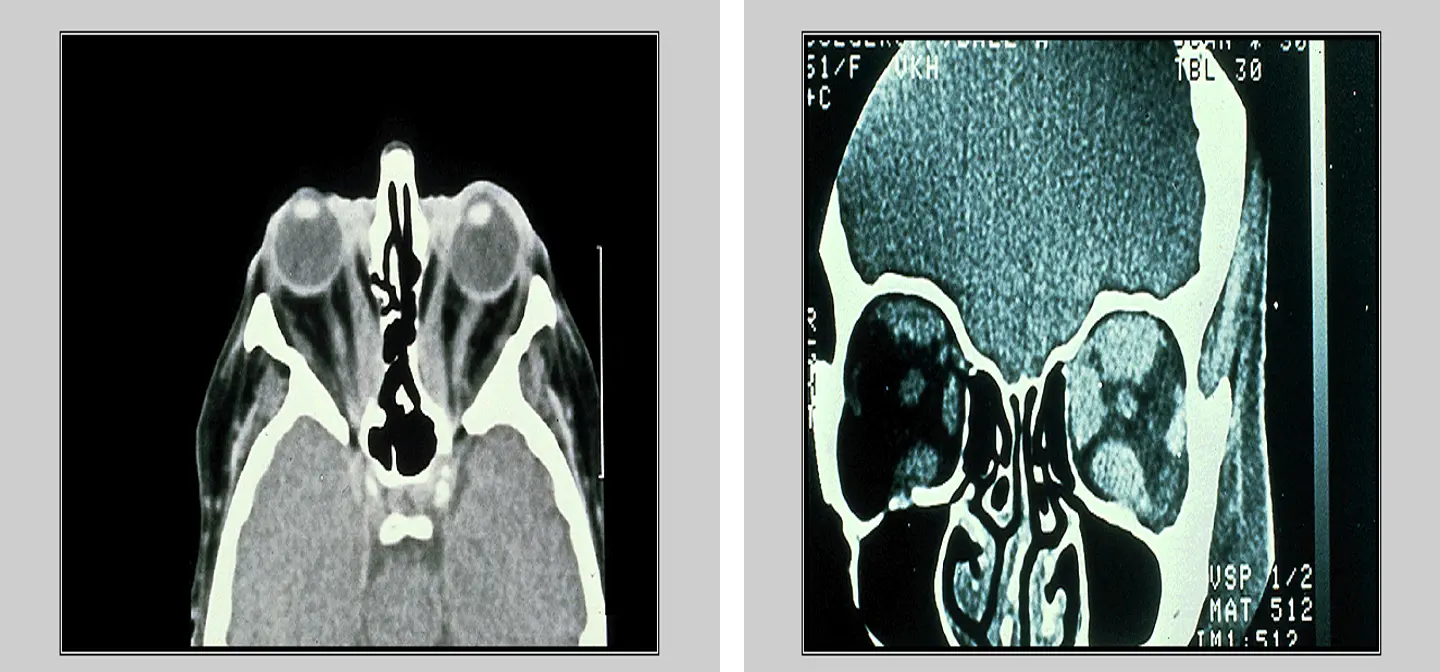

Frontal sinus mucocele

Ethmoidal sinus mucocele: